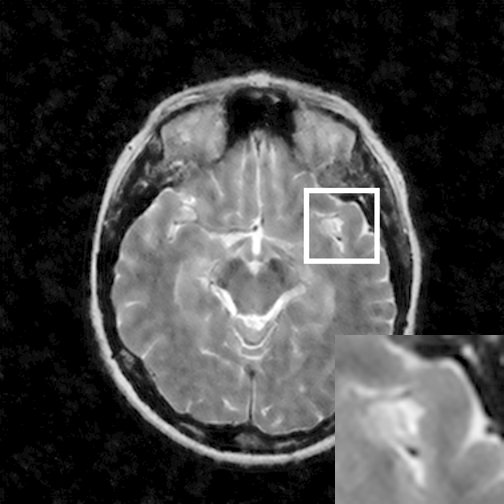

Figure 7: Reconstruction results for 20% variable density sampling. (a) Original. (b)-(h) Reconstructed images. (i)-(n) The errors of six CSMRI methods.

As shown in Figs. 7, 8 and 9, Sparse MRI and DLMRI have a lot of unpleasant artifacts, Residual learning and U-net can eliminate most of artifacts, but are not ideal for restoring image details. However, the proposed method can reconstruct better MR images, which outperforms other competitive methods in visualization of structures reconstruction and artifacts removal. Meanwhile, we can see from the absolute error residuals for three sampling experiments that the proposed MDN algorithm restores a finer detail structure than other algorithms. Moreover, we present the PSNR and SSIM values in Table I for different algorithms, sampling masks and sampling rates. It is demonstrated that the proposed method provides better reconstruction performance and visual results than other competitive methods. We can also see the obvious improvement of all algorithms over zero-filling both in visualization. In particular, a higher SSIM value of Sparse MRI appears when using 30% variable density random sampling, however, Sparse MRI generates more artifacts than the proposed MDN.